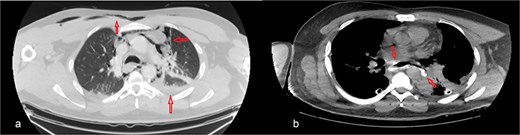

The patient was diagnosed with EP. Gastroscopy showed a 2 cm tear at 27–28 cm from the incisors and erosive esophagitis at the gastroesophageal junction (GEJ). Chest CT confirmed pneumomediastinum, subcutaneous emphysema, pleural effusion, and aspiration pneumonia (Fig. 2). The patient was transferred to the SICU for intensive monitoring. On Day 2, a right thoracotomy was performed, revealing a linear esophageal tear, food collection (mainly red meat), and a 1 cm through-and-through perforation. The procedure included debridement, defect repair with pleural patch reinforcement, and chest tube placement. The patient was monitored postoperatively in the SICU. On Day 4, the patient was extubated, and gastroscopy on Day 10 confirmed healing. An esophageal stent was placed on Day 11, with gradual clinical improvement and tolerance of oral fluids. Chest tubes were transitioned to water-seal drainage. Recurrent stent migrations occurred on Days 15, 17, and 19, requiring repositioning and eventual removal. On Day 20, bronchoscopy identified a broncho-esophageal fistula, and chest CT showed reduced leakage (Fig. 3). The patient was kept nothing by mouth (NPO) for further healing.

Chest CT scan with oral contrast showing significant reduction in the amount of leaked contrast (small rim remaining) with mild decrease in the amount of left pleural effusion and associated collapse consolidation as well as pneumomediastinum.